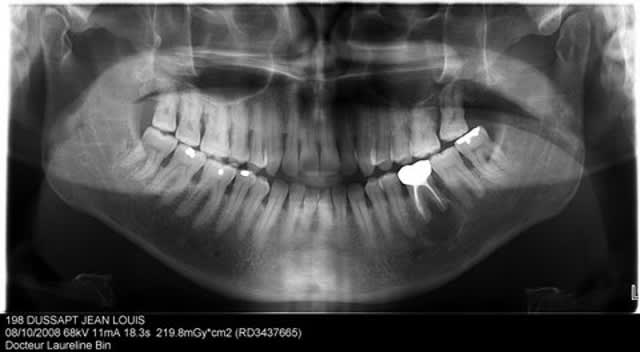

je découvre ça à la pano, la 46 a été traitée en 1980 suite à une lésion endo paro, le patient ne se plaint de rien......je surveille ou j'interviens?

C'est en effet la solution qui paraît la plus raisonnable (l'image était si petite que j'avais mal vu cette énorme lésion kystique)

- depuis quand etes vous capables de faire un diagnostic anapath (un kyste) sur une panoramique

En voyant une image comme celle là il est clair q'il s'agit d'un kyste inflammataoire mais je vais biensûr demandé une anapath.